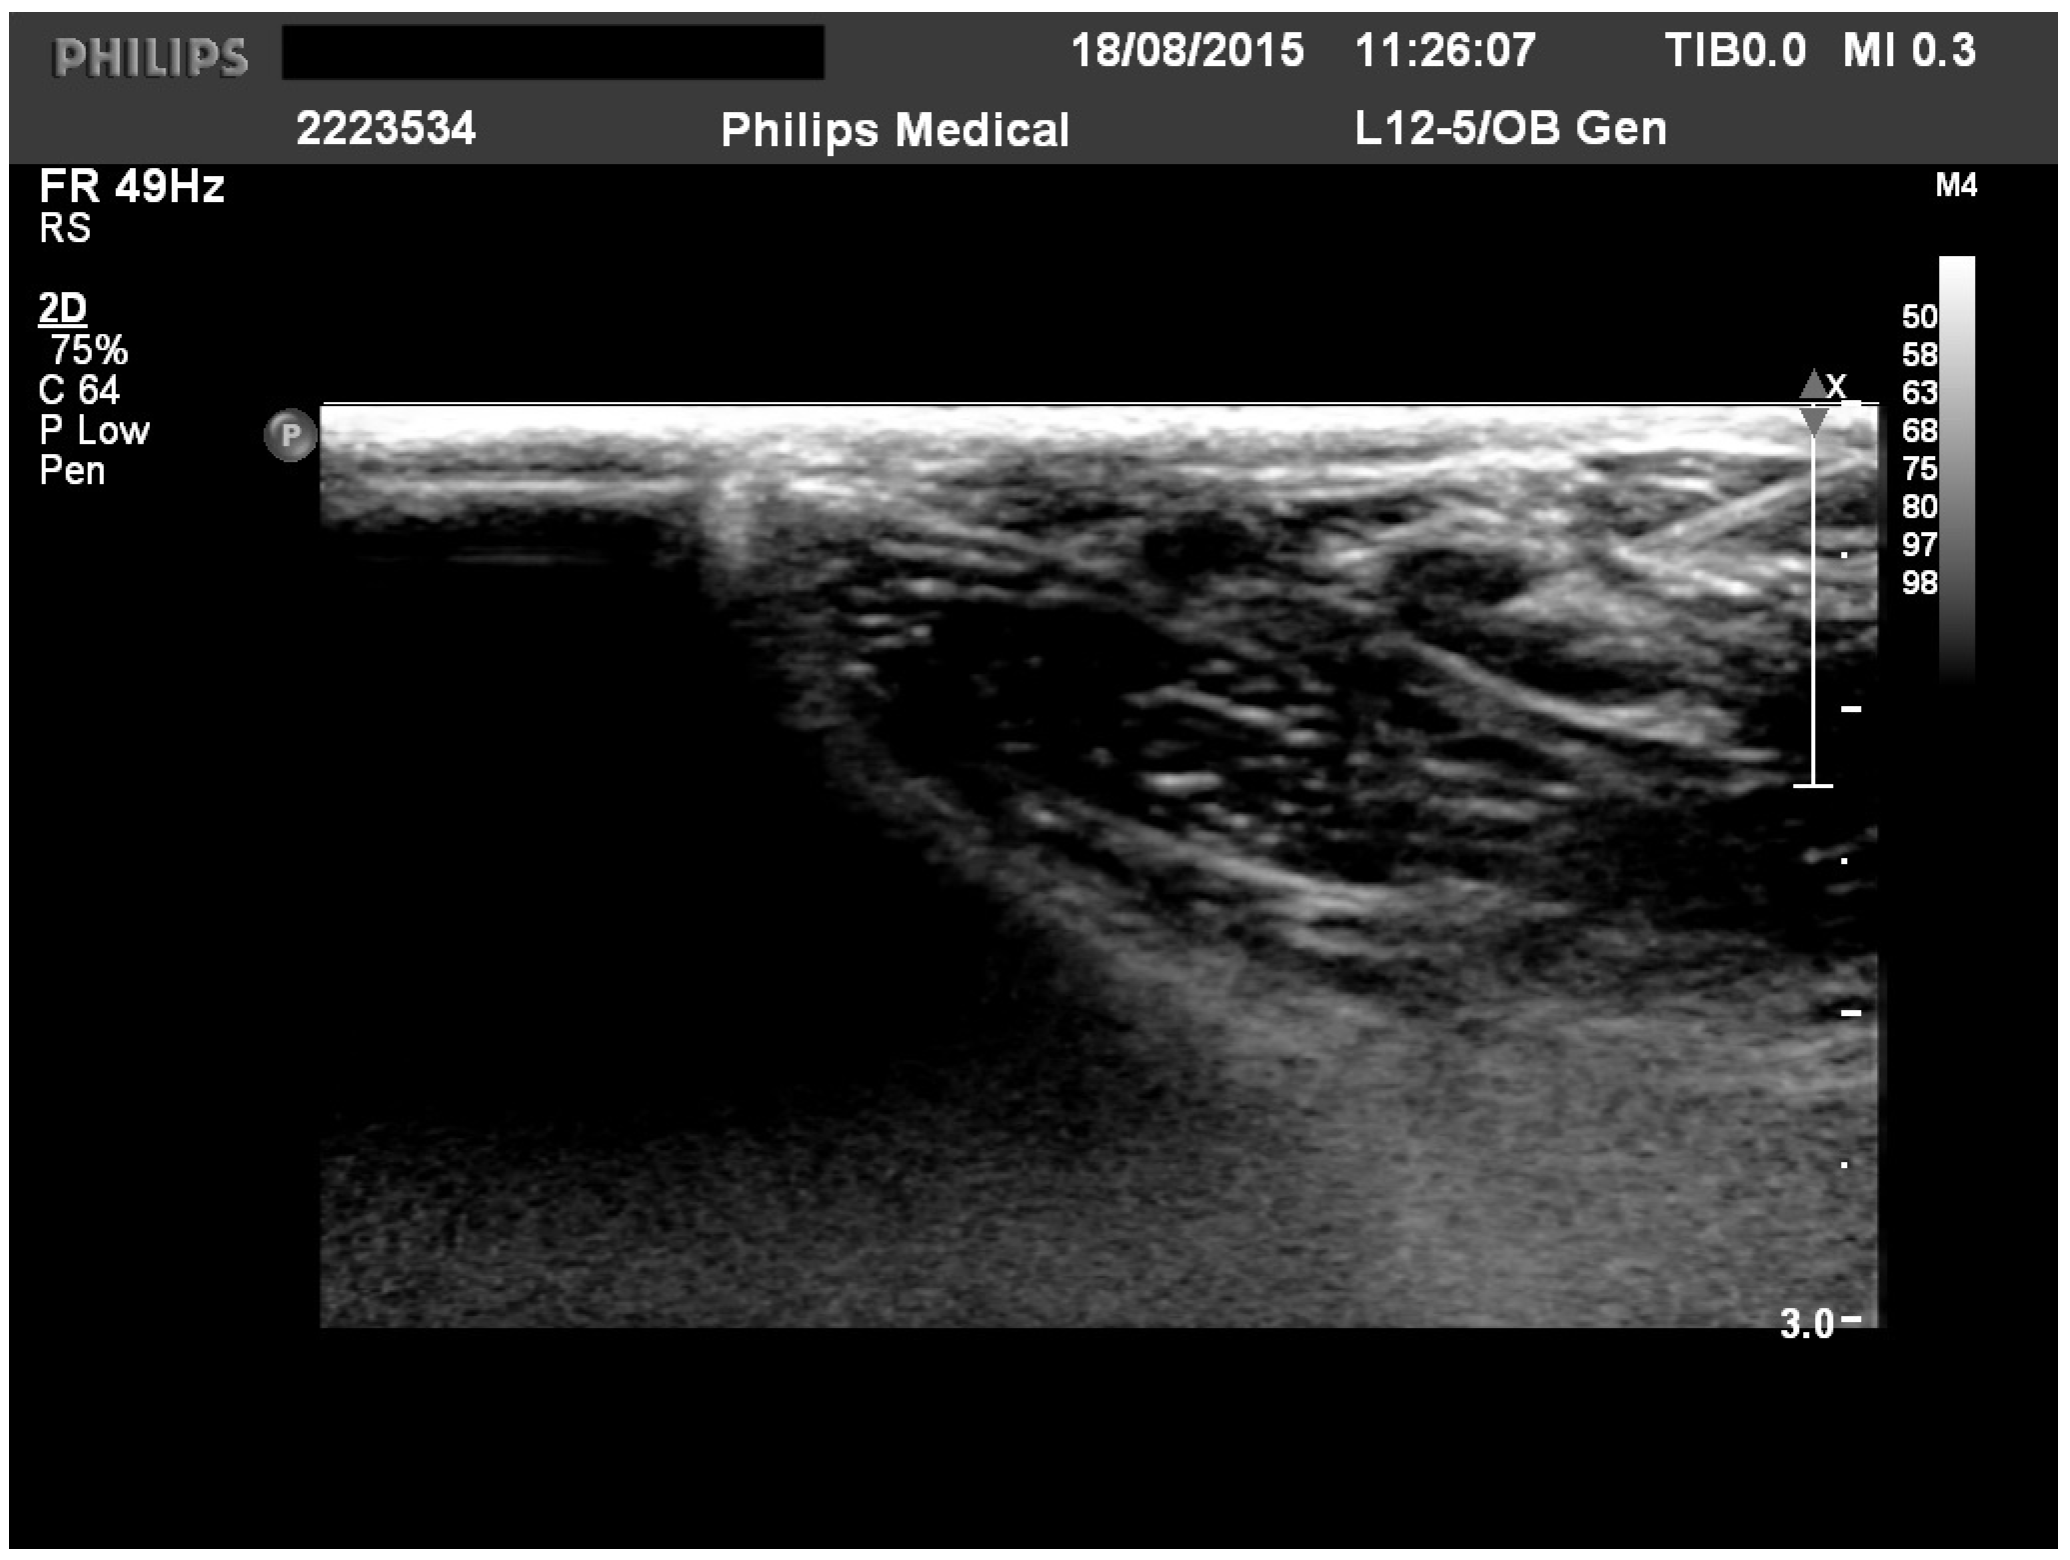

CAD cases treated by ILIT between 2014 and 2022 were retrospectively assessed regarding clinical outcome after 3 to 6 months of ILIT. Atopic dermatitis was diagnosed based on current criteria [8]. Dogs were included only when they had non-seasonal pruritus, and food allergies were excluded beforehand. Allergen solutions included aqueous allergens provided by a commercial company (Heska AG; Fribourg, Switzerland) and included up to 7 allergens (an average of 3) based on the sensitization pattern and clinical history of each dog. The allergen solution was mixed with aluminum hydroxide (Alhydrogel 2%, InvivoGen; San Diego, CA, USA) at a 1:1 ratio, and 0.2 mL was injected every 4 weeks as described previously [6]. Dogs not following this protocol were excluded from this study. Injections were performed at least 3 times and were either performed by ultrasound guidance (a board-certified radiologist, Figure 1) or by palpation (a board-certified dermatologist) into one popliteal lymph node. The efficacy of the intervention was assessed by comparing the recorded clinical presentation and the drug application at the ILIT start and at the last day of ILIT injections. The dog was clustered in the positive response group (responder dogs) when the symptomatic treatment (oclacitinib, topical or systemic glucocorticoids) could be reduced and, at the same time, the owner and investigator both evaluated the clinical presentation as improved (comparing the status at the start of ILIT and last day of ILIT injections).

Figure 1. Illustration of an intralymphatic injection into the popliteal lymph node.

Maybe performing palpation-based ILIT more often and gaining more experience could influence the results. A study by Müller et al. demonstrated that intralymphatic injections exhibit comparable efficacy to subcutaneous injections across different protocols. This finding suggests that experienced veterinarians can perform accurate palpation-based injections without the need for ultrasound guidance [5]. It should be noted that even injections performed by ultrasound guidance may be inaccurate, especially in non-cooperative dogs. Furthermore, from ultrasound imaging, the palpation of and injections made in the popliteal lymph nodes can be difficult due to their location in the popliteal space surrounded by subcutaneous fat and muscle tissue. These issues may clearly influence the ILIT outcome.